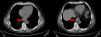

Hombre de 64 años de edad, sin antecedentes de importancia, a quien se le realizó una TAC de abdomen por sospecha de urolitiasis. El paciente negó disfagia u alguna otra sintomatología digestiva. La exploración física sin datos relevantes y los exámenes de laboratorio sin alteraciones. En la TAC se identificó la presencia de una lesión ovoidea, dependiente de la pared del esófago, de situación retrocardiaca y parasagital izquierda, con diámetros mayores de 39 x 29mm en el plano axial, presentaba contenido con atenuación de 20-30 UH, con paredes regulares que muestran discreto reforzamiento tras la administración material de contraste (fig. 1).